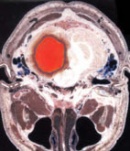

• Компютърна томография (КТ) на глава

Компютърна томография (КТ) на глава Компютърна томография (КТ) на глава

Компютърна томография (КТ) на глава